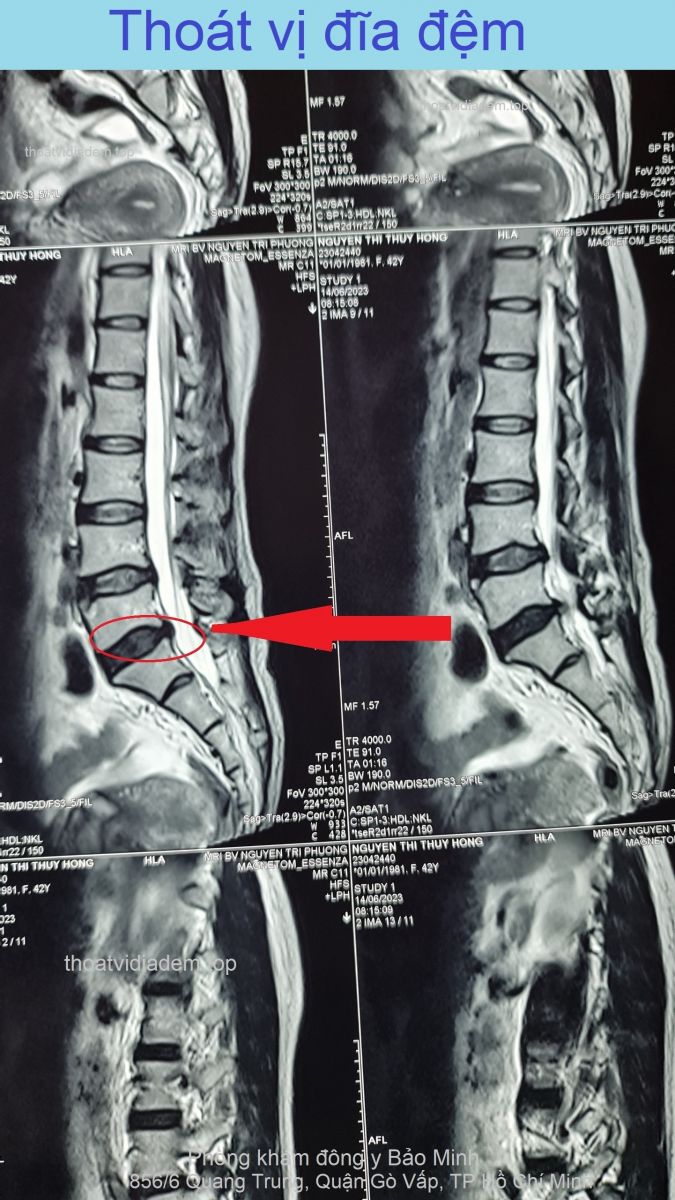

Thoát vị đĩa đệm, hẹp nặng ống sống, hẹp lỗ liên hợp, chèn ép rễ thần kinh Thoát vị đĩa đệm, hẹp nặng ống sống, hẹp lỗ liên hợp, chèn ép rễ thần kinh

Đây là trường hợp bị thoát vị đĩa đệm nặng, chụp cộng hưởng từ cột sống thắt lưng, bác sĩ chuyên khoa chẩn đoán hình ảnh kết luận: Thoái hóa mất nước đĩa đệm cột sống thắt lưng tầng L4-L5, L5-S1. Thoát vị đĩa đệm tầng L4-L5 ra sau #8mm, thể trung tâm, gây hẹp nặng ống sống, hẹp lỗ liên hợp, ép rễ thần kinh L5 hai bên. Thật may mắn tôi đã chữa khỏi bệnh cho anh, đã đi làm bình thường được 8 tháng. Hãy nghe tiếng ...